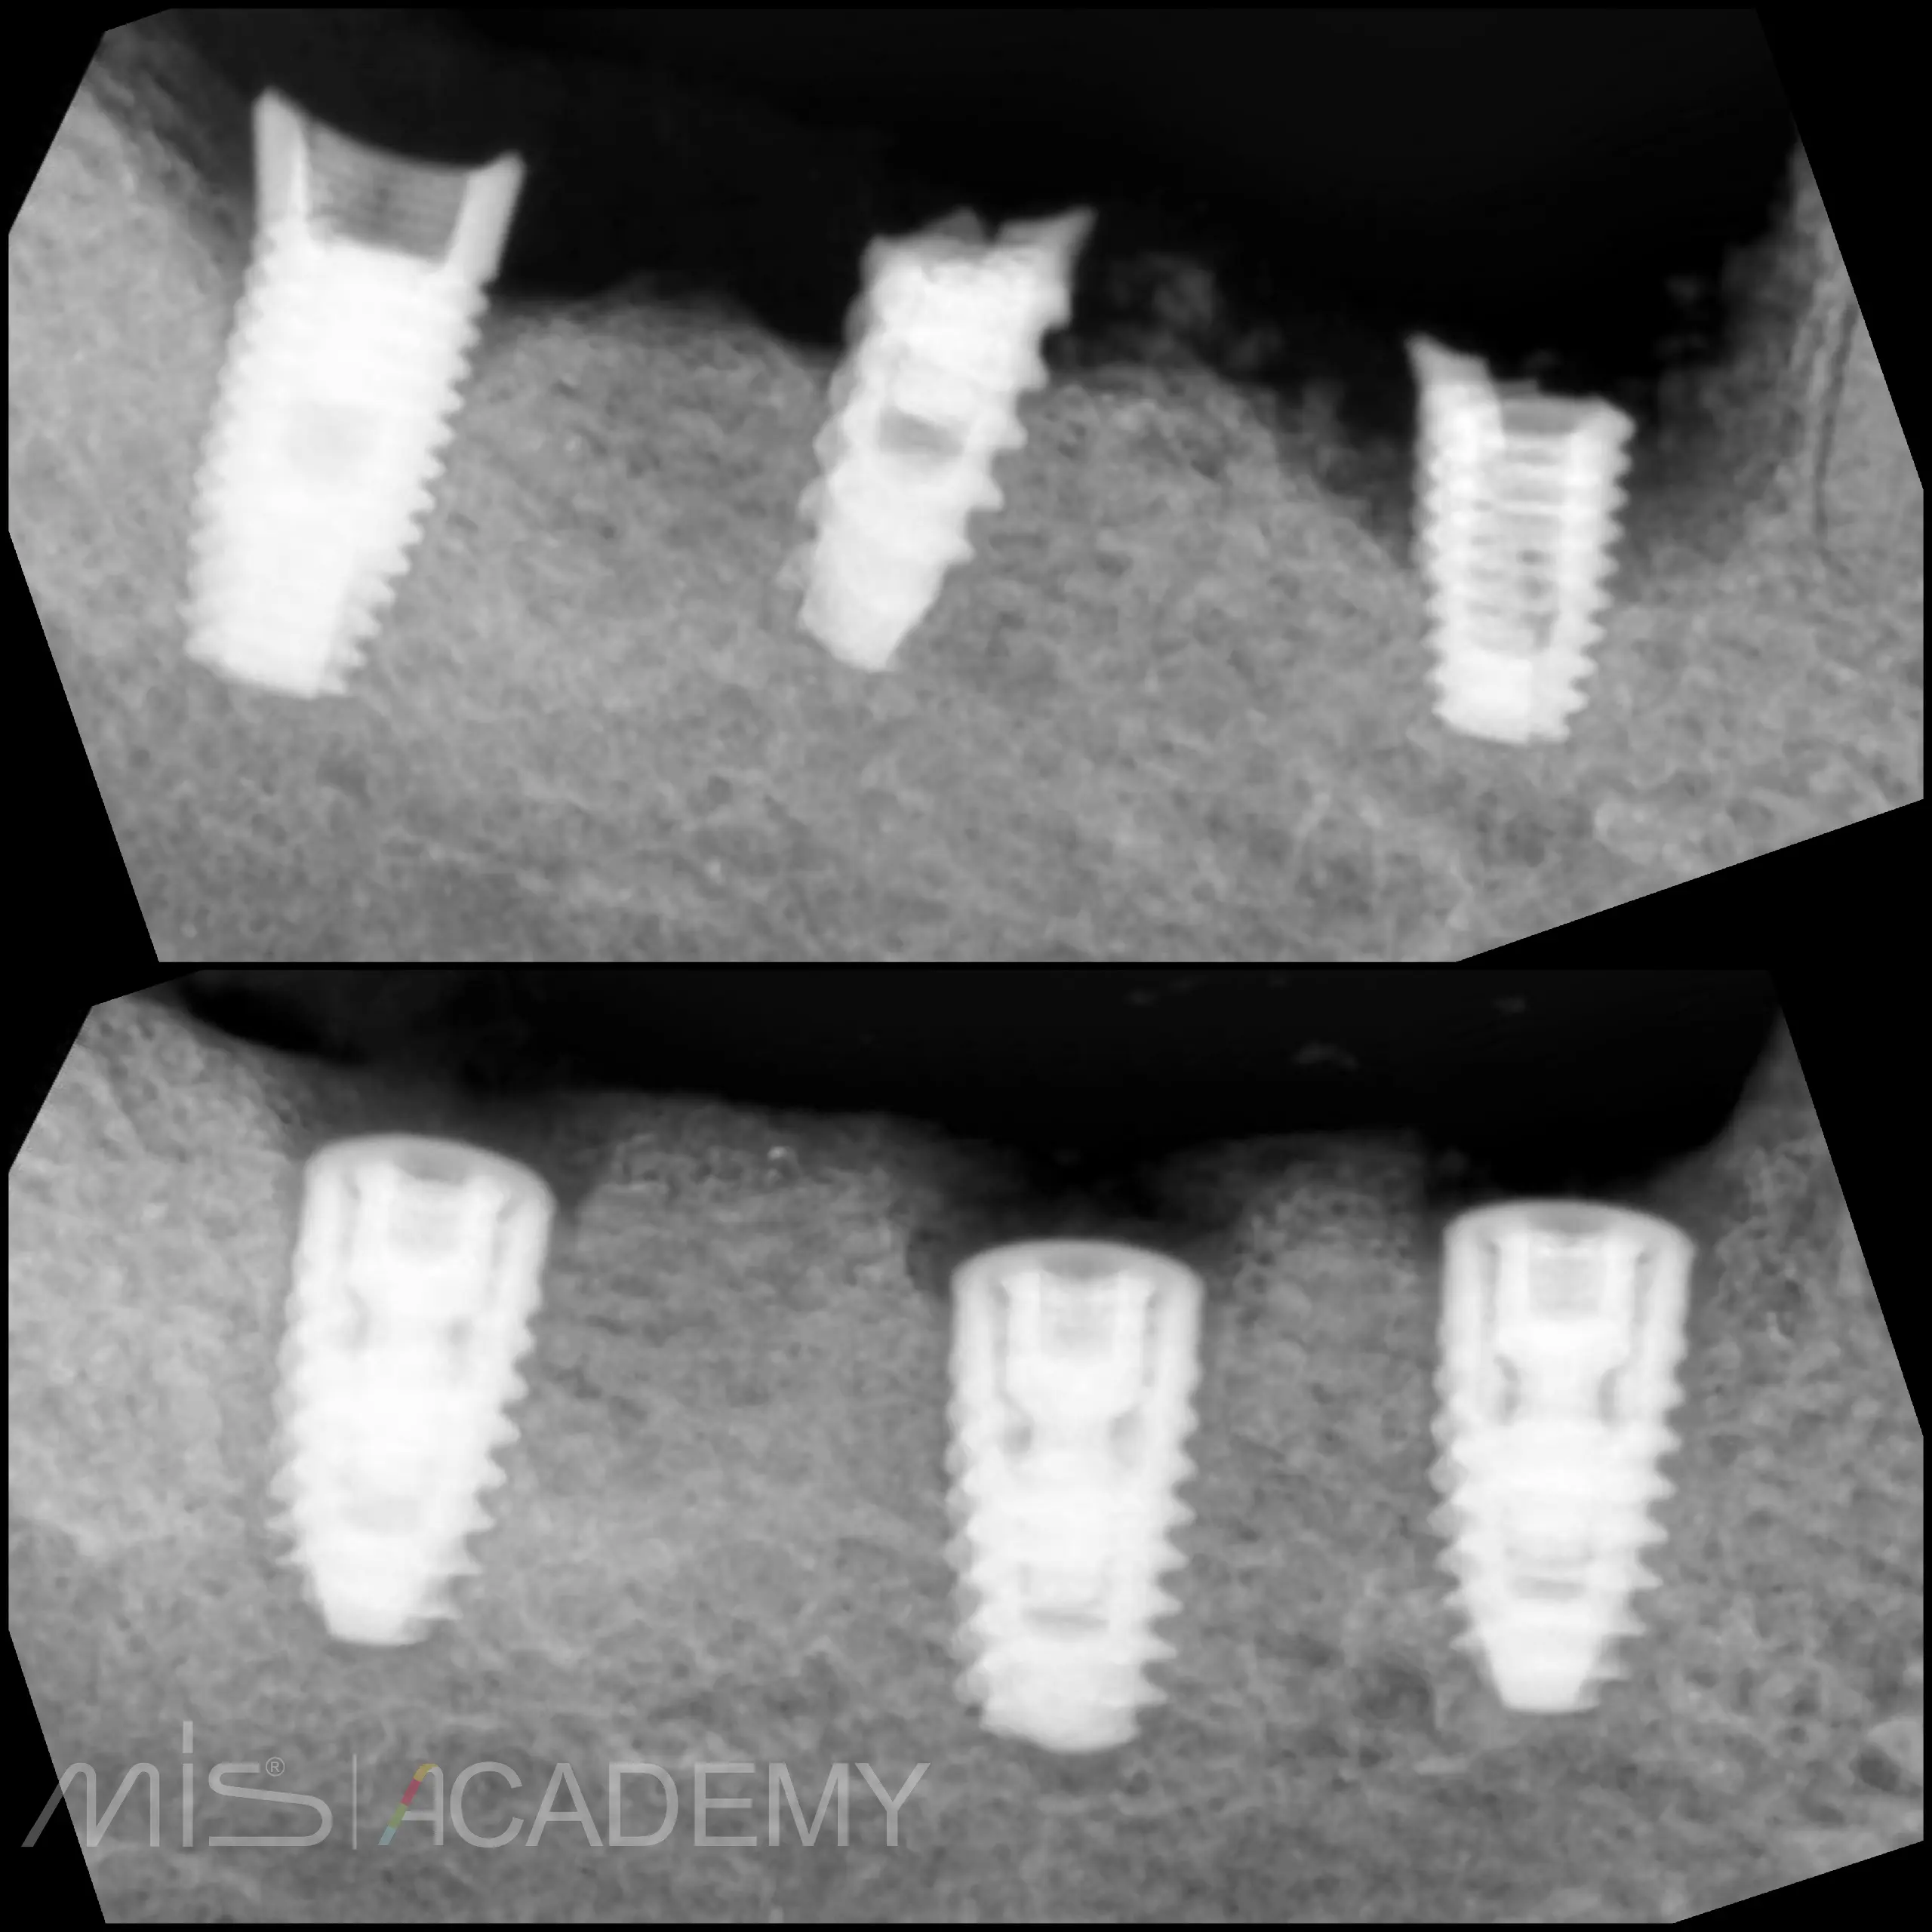

— Удаление несостоятельных имплантов.

— Костный графт + мембрана.

— Установка имплантов MIS C1.